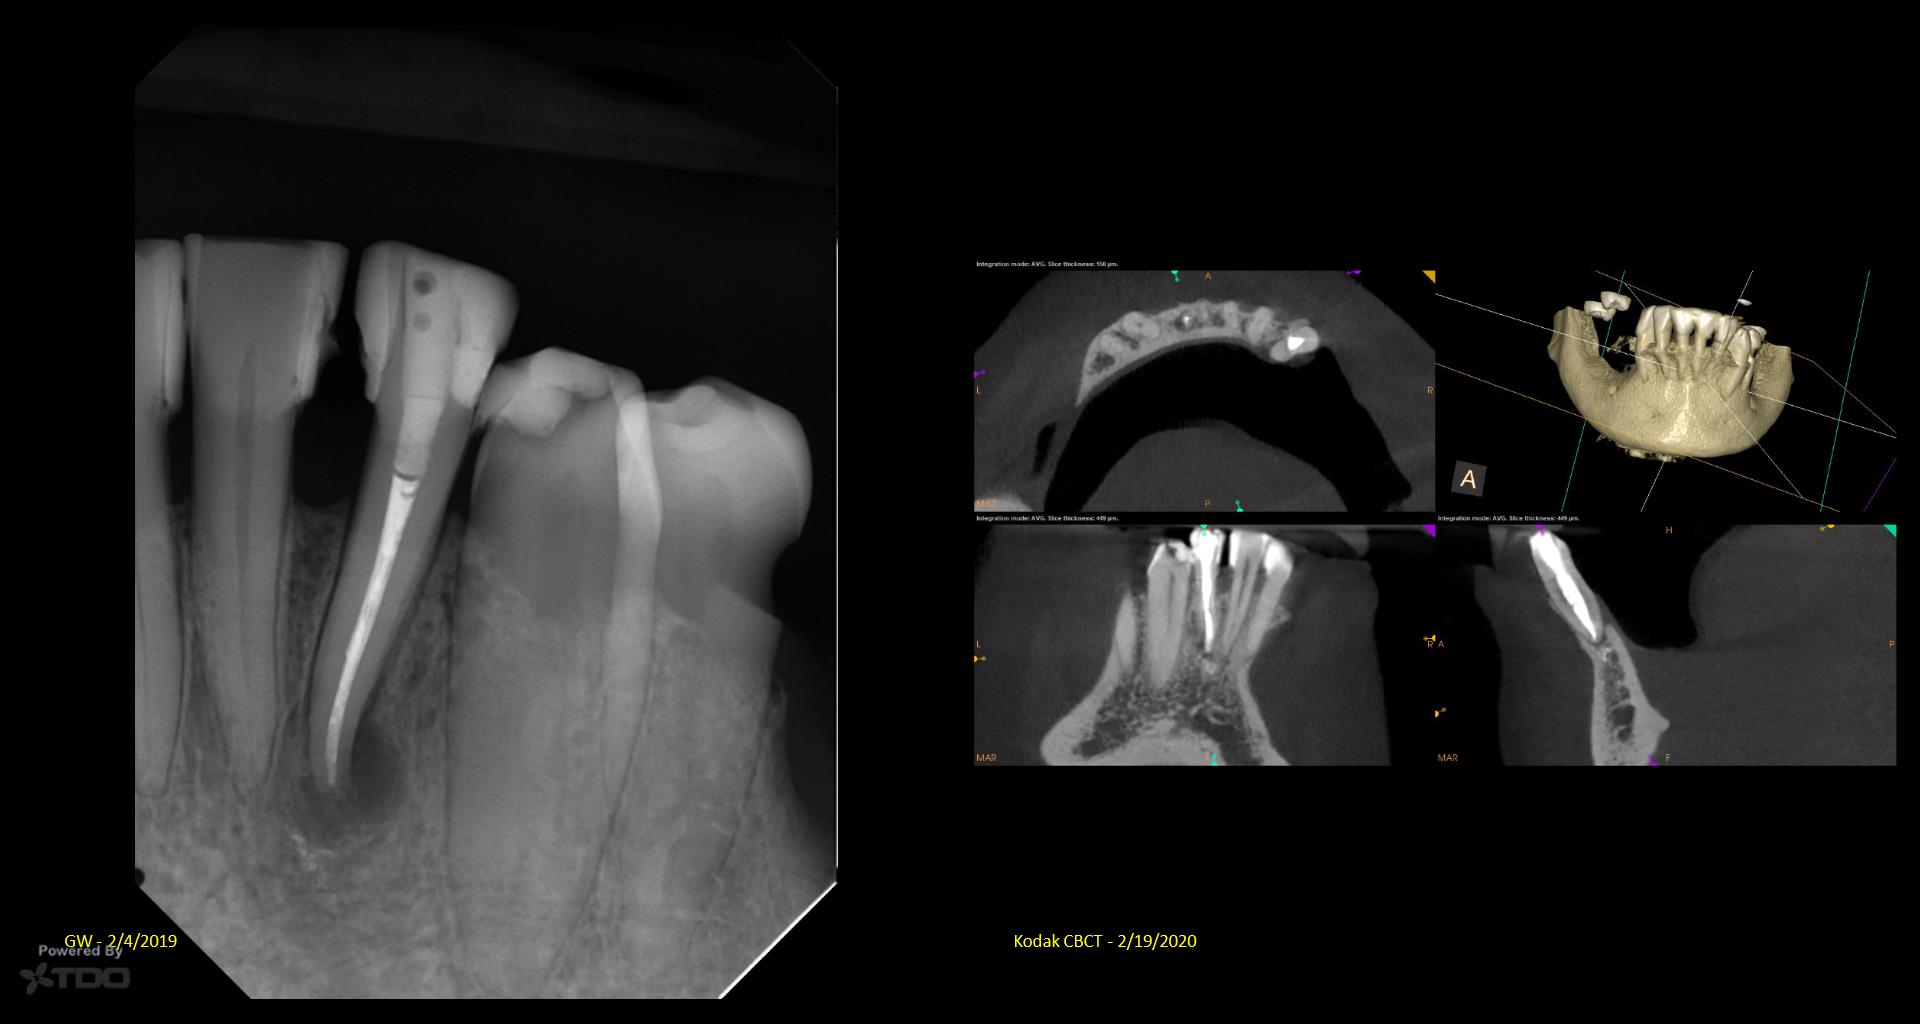

It’s a little embarrassing…but I have been treating a tooth of Joy’s for 5 years….Multiple CaOH visits over those 5 years. Coulod never get the area to resolve. Finally tried a GW on it…..1 yr recall today. gbc